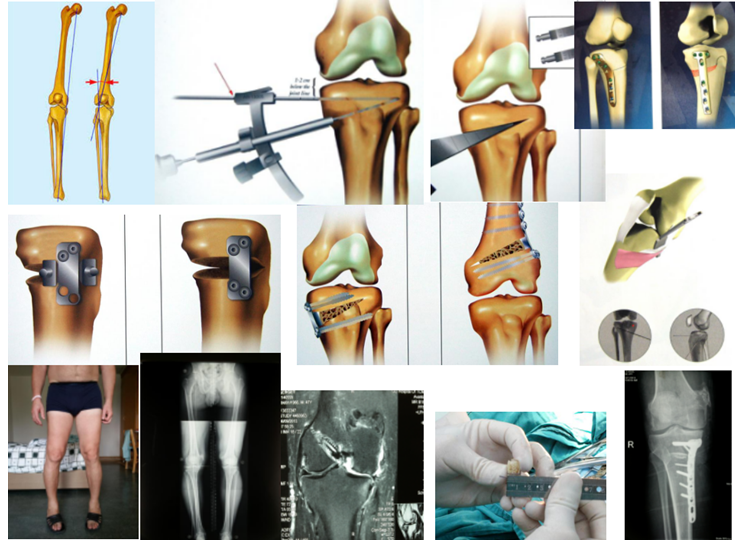

HTO全称是指胫骨高位截骨(High Tibial Osteotomy,HTO)的英文缩写。简单来说,这是一种保留原有的关节,通过矫正膝关节负重力线、阻止软骨的进一步磨损、增加关节稳定性、缓解疼痛、改善膝关节功能,

从而避免或尽可能的推迟关节置换的一种“保膝”手术。

通过经过高位截骨,矫正力线,适用于合并严重内翻的膝关节骨性关节炎,可延缓关节炎进展,保留了膝关节的正常活动功能—称之为保膝治疗.随着技术水平的提高,内固定材料的稳定性增强,此术式用于早中期的膝关节关节炎的治疗,延缓内侧关节的破坏,延长膝关节的使用寿命,推后或避免膝关节的置换,进而缓解疼痛,提高患者生活质量。

胫骨高位截骨与膝关节置换治疗膝关节炎相比,具有手术时间短、创伤小、恢复快、术中及术后康复基本无痛,关节原有结构未破坏。通常情况下,行HTO的患者,术后第2天就开始患肢部分负重,4周开始逐渐增加负重,6~8周后可以完全负重锻炼;常规在手术3个月后,患者的日常的劳动和体育运动不受影响。因膝骨关节炎行HTO的患者,术后功能恢复良好,膝关节评分较术前明显提高,患者对术后疗效满意。

HTO“保膝”治疗主要针对临床上两种常见的膝关节疾病———骨关节炎和胫骨平台骨折,通过微创手术,最大限度保护原有膝关节组成,减少术后并发症的发生,实现早期功能锻炼和恢复。